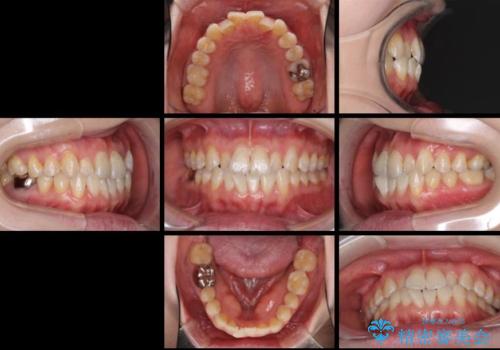

前歯のデコボコを治したい インビザラインによる矯正治療

- 前歯のデコボコを治したいとのことで来院された患者様です。

上下顎ともに歯列全体の後方移動とIPR(歯と歯の間を削る)によってデコボコが解消するように設計し、インビザラインにより治療を行うこととしました。